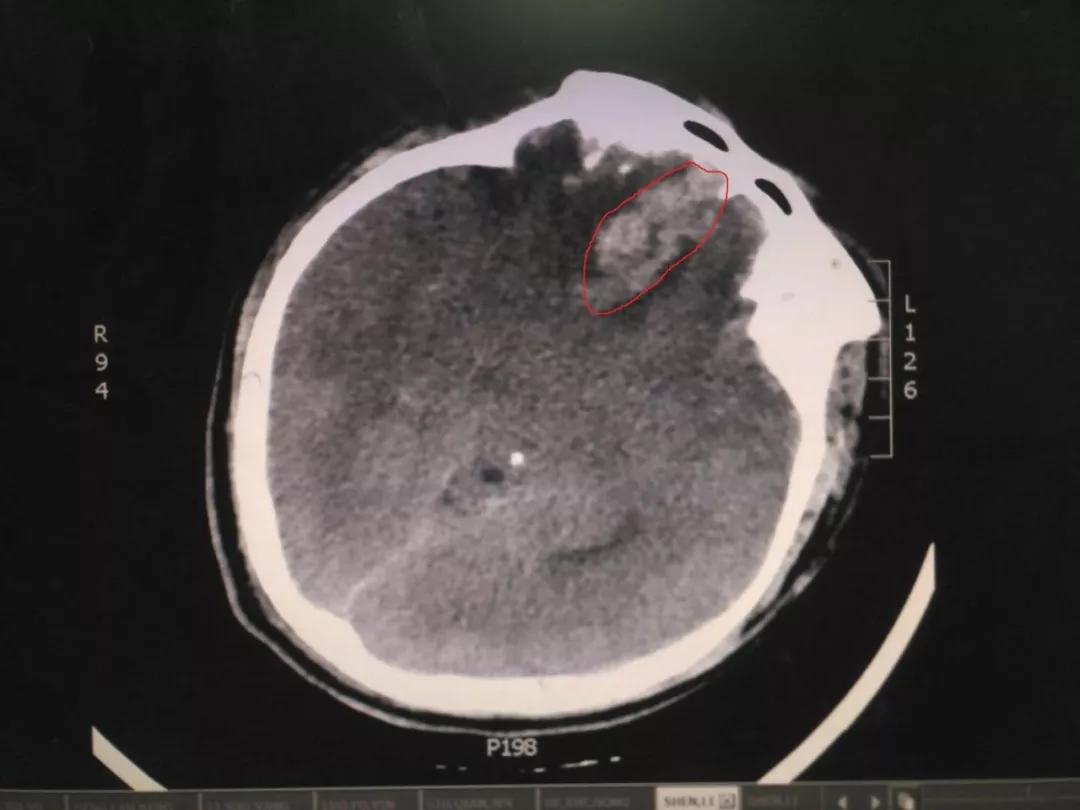

近日,我神经外科收治了一位29岁因意外头颅严重外伤患者。患者亲友叙述,患者在摔倒后头痛剧烈、意识不清。王占尧主任医师立即安排为该患者查体,各个检查科室也为患者开通绿色通道,大家一起为这个29岁的年轻人鼓劲加油。

初步诊察发现患者右侧瞳孔散大,CT结果显示右侧额叶脑挫裂伤,部分血肿位于前颅凹底,位置深,清除困难,这给治疗带来了一定的难度。王占尧主任医师随即决定应用神经内镜辅助清除血肿,并采用右侧额颞弧形切口,避免采取传统的双额冠状切口,骨窗大小仅有4cmX4cm,大大减少了手术创伤,也相应减少了住院手术的费用,减轻了患者负担。术后第二天,患者意识恢复,复查CT显示血肿清除效果满意。